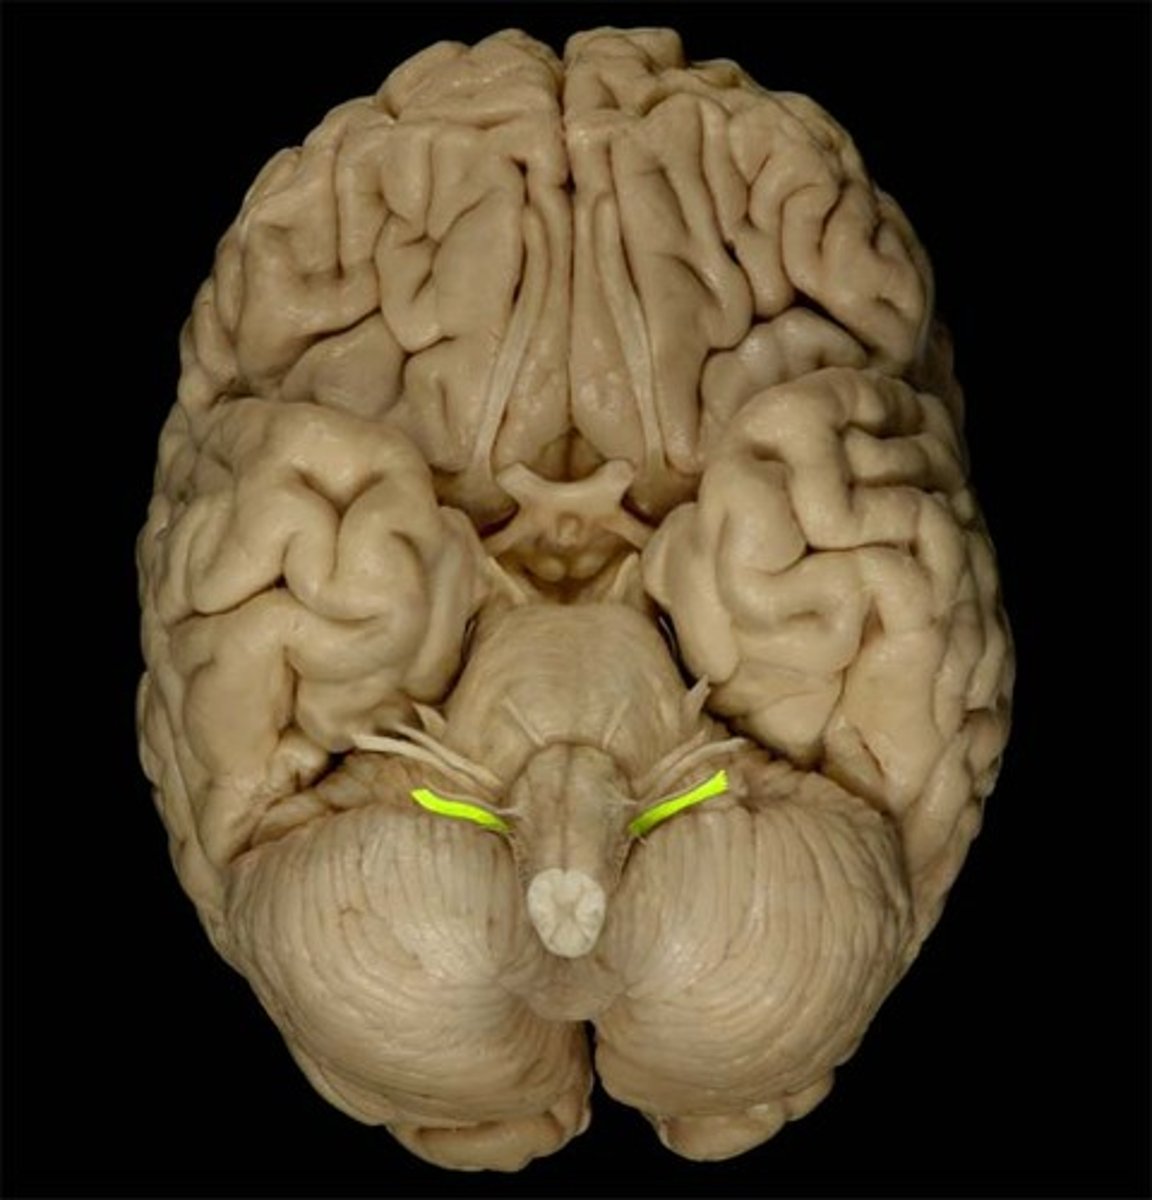

medulla oblongata

most inferior part of the brain stem; regulates breathing, heart rate, & blood pressure

the 'olives'

oval-shaped structures located on the anterior surface of the medulla, lateral to the pyramids

accessory nerves

controls swallowing via vagus nerves

hypoglossal nerves

controls tongue movement; speech